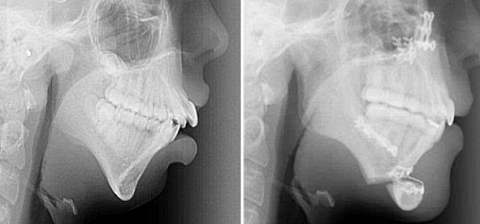

图片3.png

矫正前后,龅牙得到了理想的解决